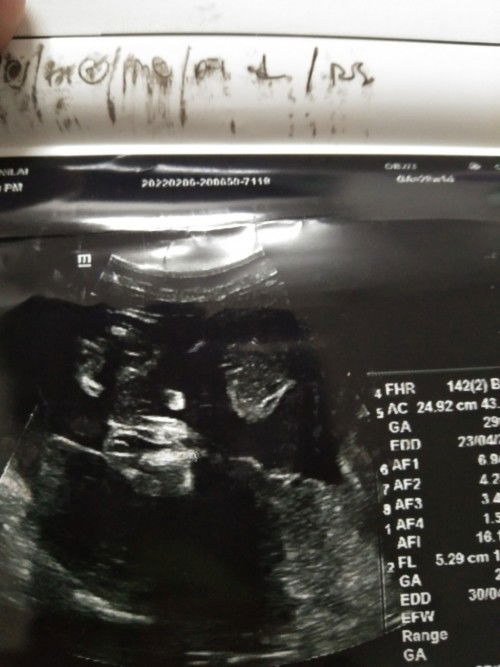

Sekadar ingin kepastian

Sya dh buat 2kli scan..first doc ckp boy..second xpasti..agk2 ibu2 smua pic scan ni boy ke girl#ingintahu